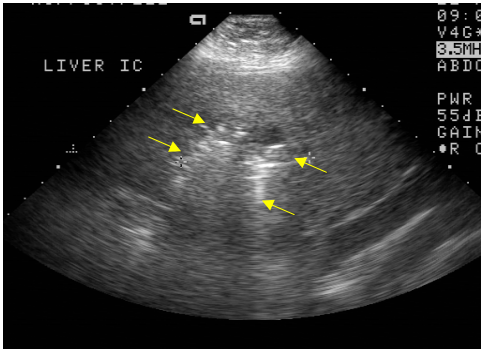

63 中年女性有上腹部疼痛,其超音波檢查如附圖,箭號所指為病灶,則下列敘述何者錯誤?

(A)此為肝右葉之肋間掃描影像 (B)高回音性病灶可能為氣體所致 (C)病灶可能為肝膿瘍 (D)病灶為典型之肝癌